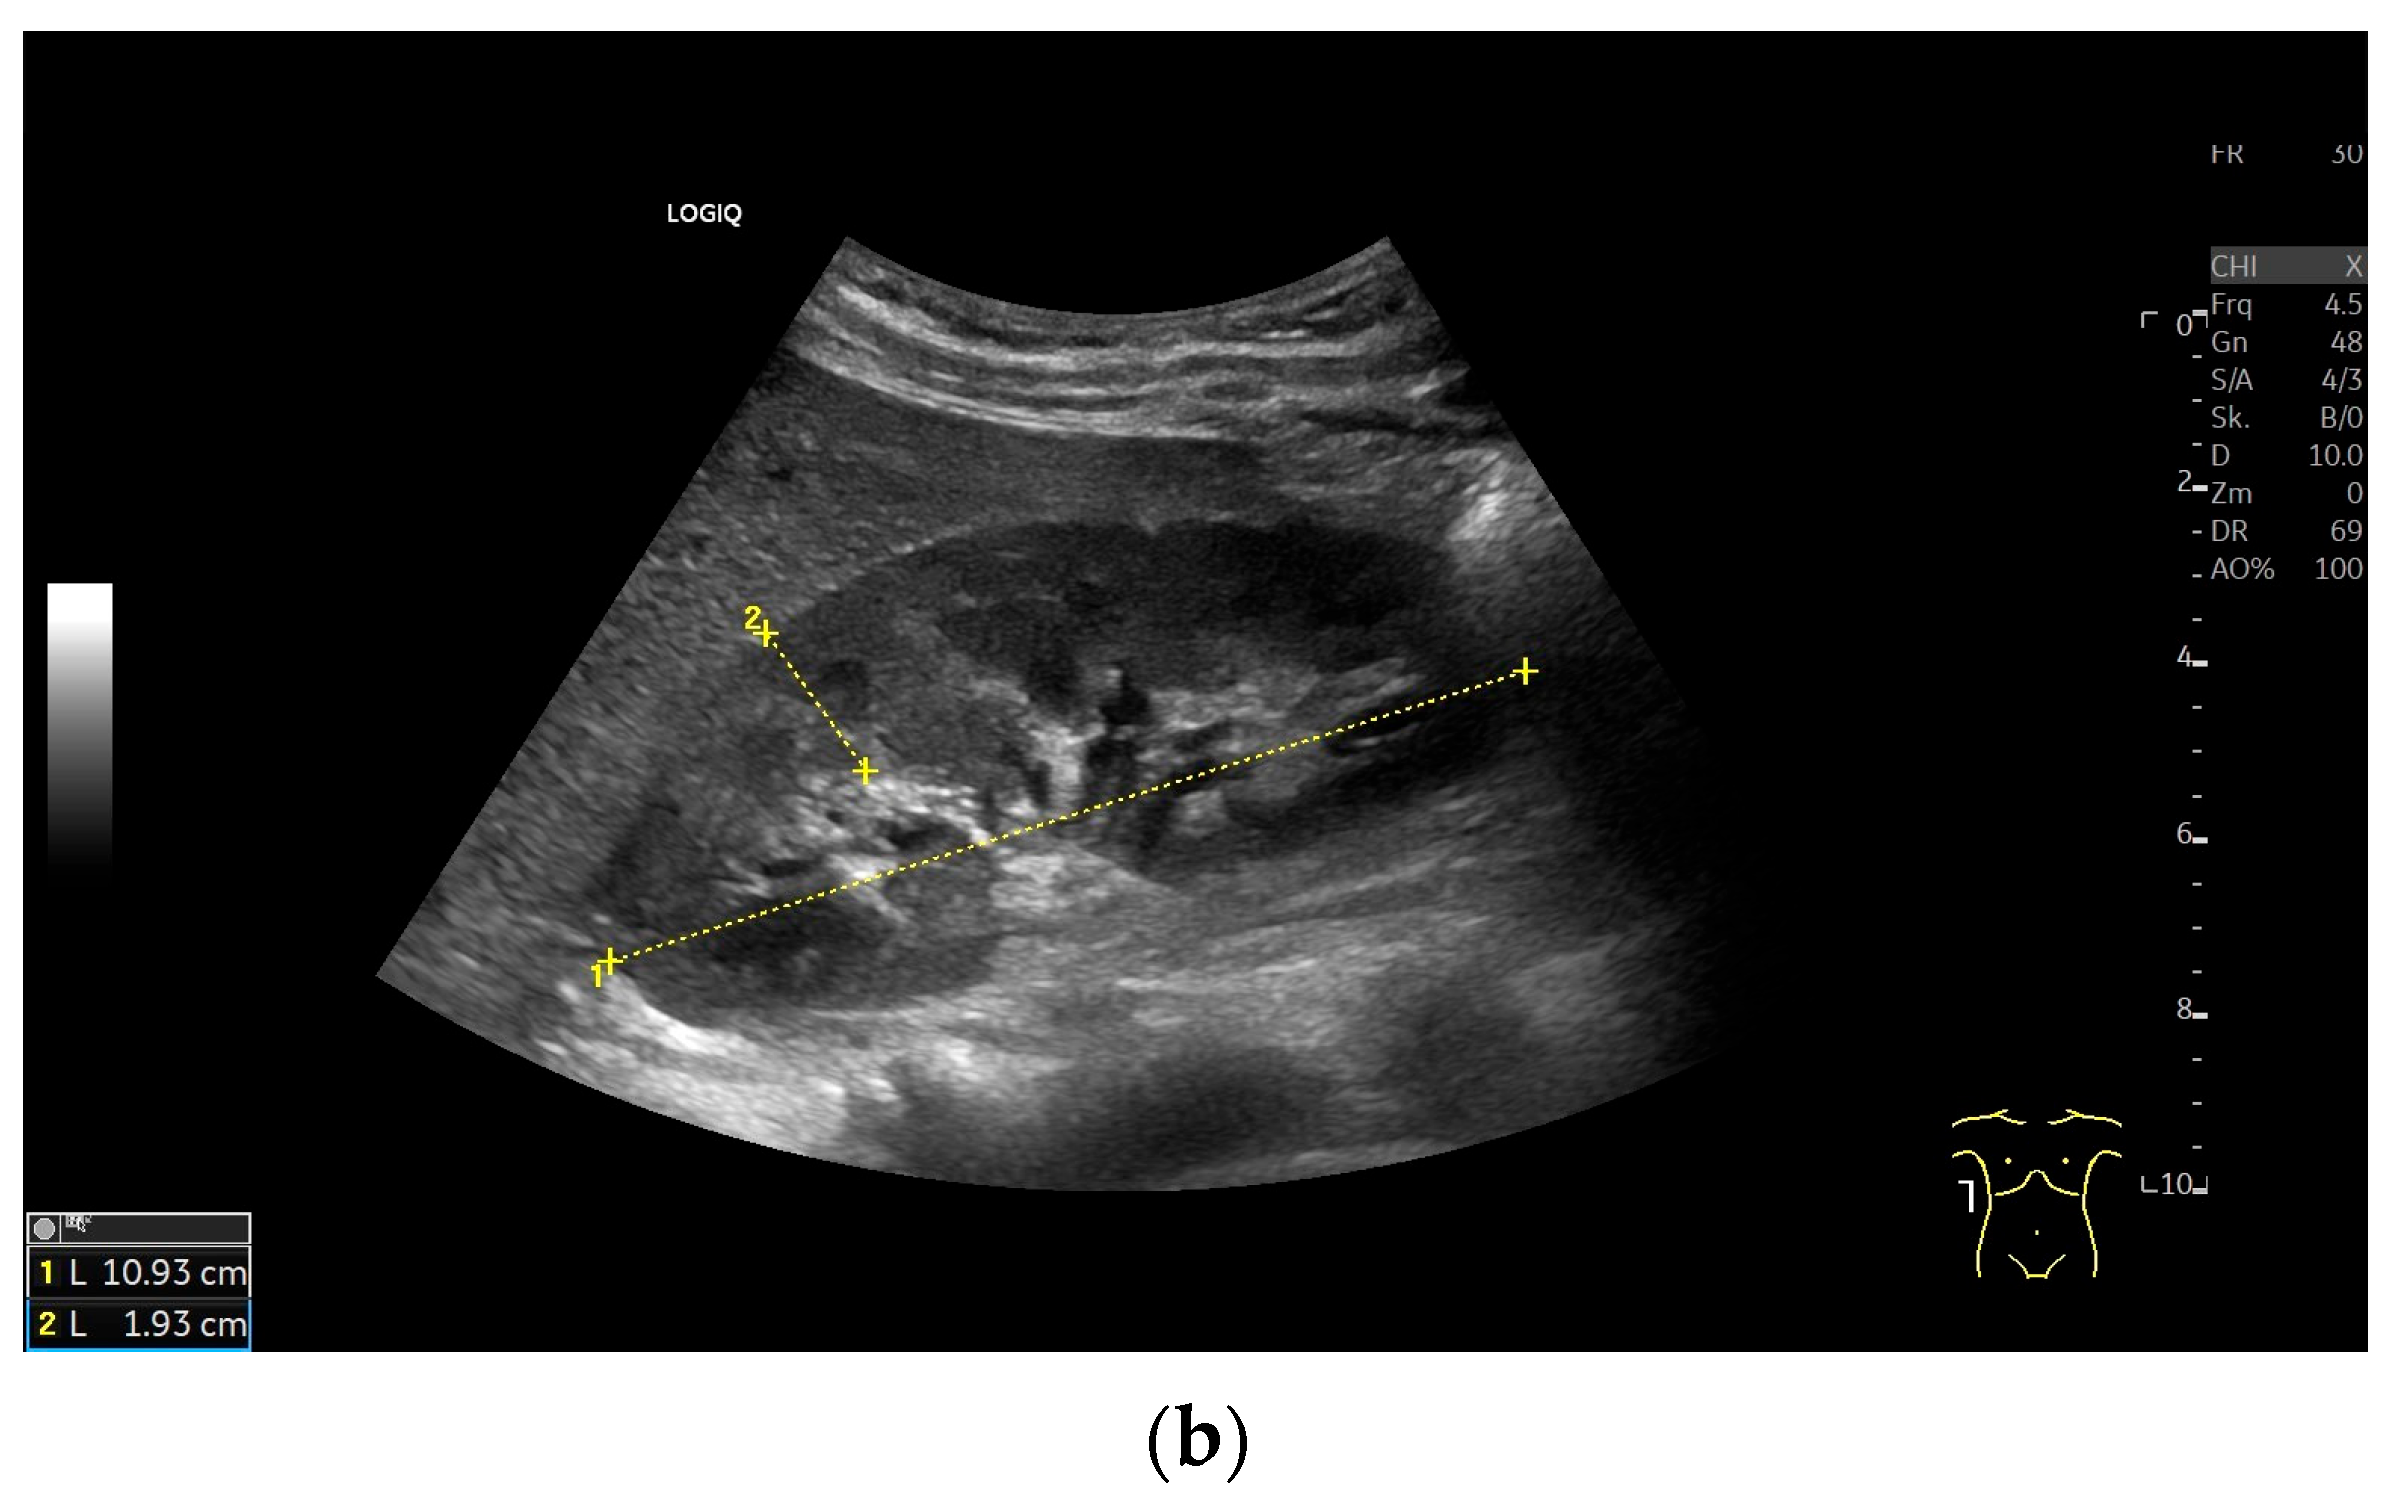

Imaging Techniques and Protocol

| Length/maximum pole distance | Maximum length distance from the kidney contour at the upper pole to the contour at the lower pole. If the parenchymal margin at the upper and lower poles is of different thickness, the kidney is displayed tangentially. |